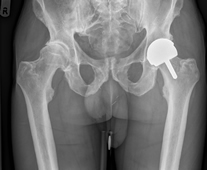

X-ray showing a Left Birmingham™ Resurfacing Hip Replacement. Enlarge